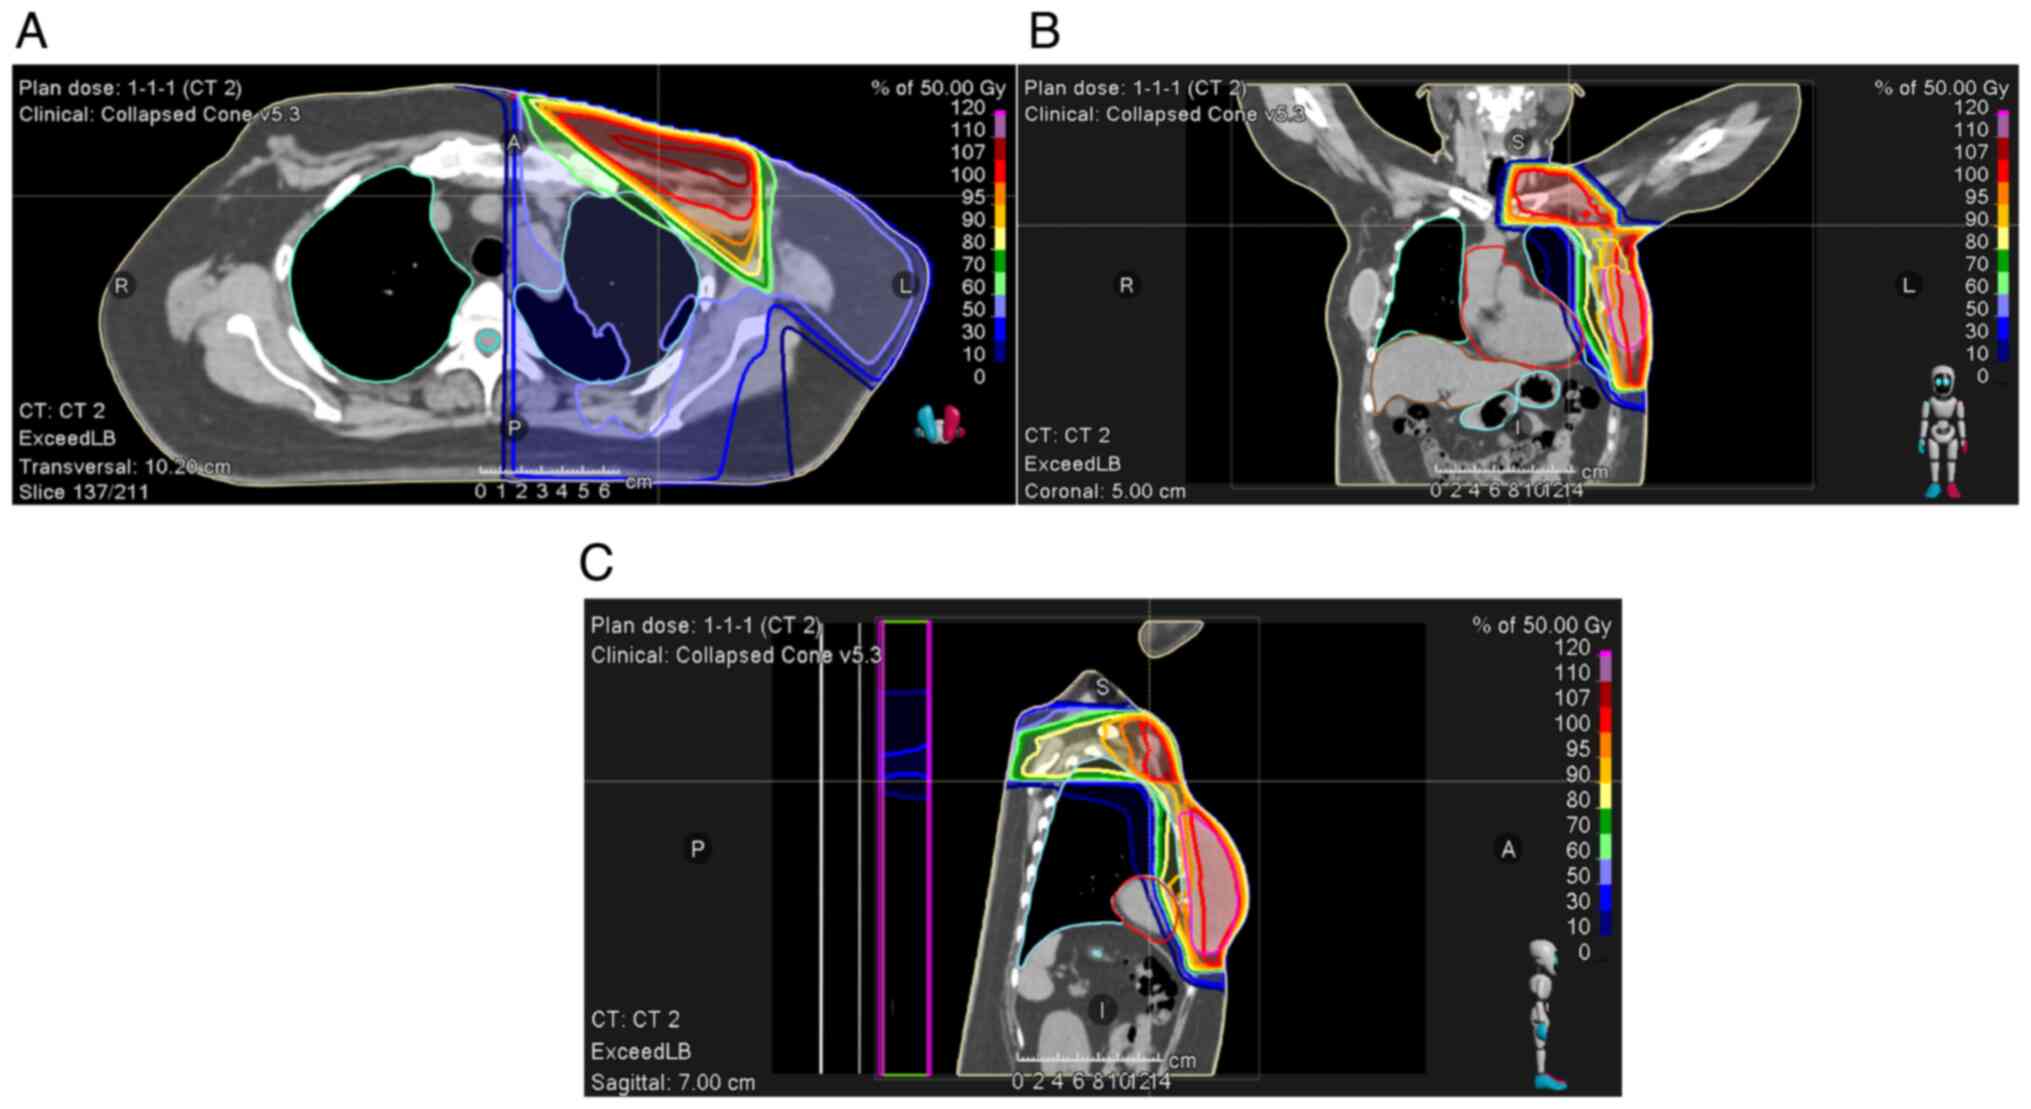

Figure 1

Radiation dose distribution of three-dimensional chemoradiotherapy for initial treatment. (A) Axial view. (B) Coronal view. (C) Sagittal view.

A 52-year-old woman underwent left total mastectomy with axillary dissection and right total mastectomy for pT2N3aM0 stage IIIC breast cancer (left breast; invasive ductal carcinoma, estrogen receptor-positive, progesterone receptor-negative, Ki-67 25%) and pTisN0M0 stage 0 breast cancer (right breast; ductal carcinoma in situ, estrogen receptor-positive, progesterone receptor-positive, Ki-67 5%). Post-surgery, the patient received adjuvant therapy consisting of four cycles of dose-dense doxorubicin and cyclophosphamide chemotherapy, four cycles of dose-dense paclitaxel monotherapy, tamoxifen hormone therapy, and tangential irradiation therapy of 50 Gy in 25 fractions (Fig. 1). The radiation therapy caused erythema at the irradiation site, which improved after application of dimethyl isopropyl azulene ointment (dermatitis radiation grade 2). On day 366 after mastectomy and 20 days after the completion of radiation therapy, the adjuvant therapy with abemaciclib (300 mg/day) was initiated. On day 85 of abemaciclib treatment and 157 days after completion of radiation therapy, the patient presented with a history of cough, fever, and dyspnea for 1 week. CT findings were suggestive of interstitial pneumonitis (Fig. 2), and the patient was admitted for suspected drug-induced pneumonitis or radiation pneumonitis. The pneumonitis was classified as grade 3 according to the Common Terminology Criteria for Adverse Events, and abemaciclib was discontinued. Ampicillin/sulbactam treatment was initiated because bacterial pneumonia could not be ruled out.